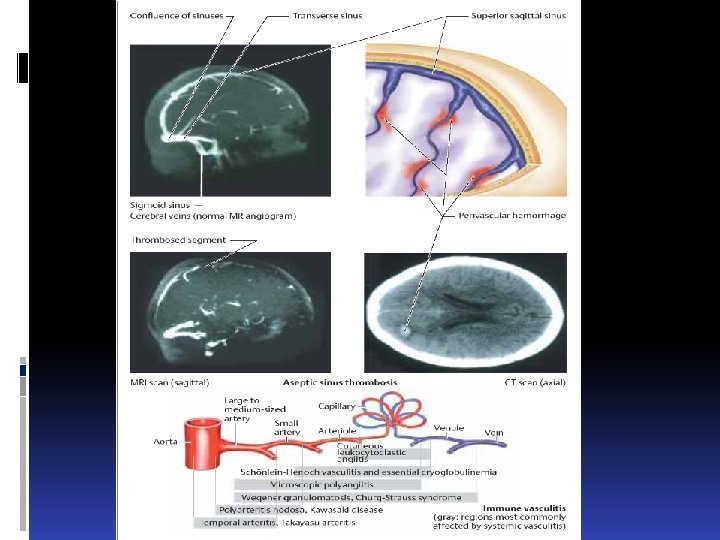

геморрагические инсульты Субарахноидальное кровоизлияние subarachnoid hemorrhage Разрыв внутричерепной аневризмы Расслоение внутричерепной артерии Геморрагический диатез Тромбоз мозговых вен Травма Hemorrhagic diathesis Trombosis of brain veins Trauma

геморрагические инсульты Субарахноидальное кровоизлияние subarachnoid hemorrhage Разрыв внутричерепной аневризмы Расслоение внутричерепной артерии Геморрагический диатез Тромбоз мозговых вен Травма Hemorrhagic diathesis Trombosis of brain veins Trauma